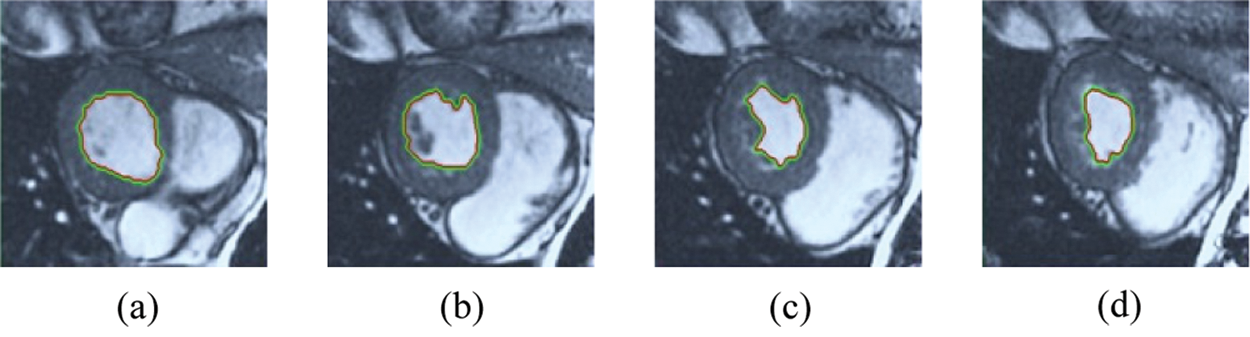

The BRW, HSRW, and ERW medical imaging segmentation schemes are executed on MATLAB, and examined on a short-axis of 3D multi-slices CMRI dataset [27]. Several segmentation performance metrics are utilized such as Dice Metric (DM), the Haussdorff distance (HS), and the Peak signal to noise ratio (PSNR). The BRW, HSRW, and ERW segmentation schemes are executed on a short-axis of 3D multi-slices CMRI datasets. The same multilayer CMRI dataset is segmented using various random walk methods. The presented results were obtained through using BRW, HSRW and ERW methods on five different groups of patients; each group contains 25 subject of multilayer CMR dataset. Experimental results illustrate that the BRW method can achieve a good segmentation of the LV cavity. The results of the HSRW algorithm have very comparable similarities to BRW, but with a slightly less efficiency and a much higher execution rate. Pre-calculations reduce the performance online time in offline mode. The average time of HSRW equals to 0.09 seconds for each slide. Raising the rate of K will improve the comparison and makes the process of segmentation more precise, but also reduces the execution time. The ERW technique results illustrate that this method has the greatest efficiency of segmentation. Figs. 5 to 7 show the resulting images of the BRW segmentation method on five sets of sample data. HSRW with pre-calculation segmentation method is applied on the same sets of sample data and illustrated in Figs. 8 to 10. Figs. 11–13 show the high efficiency segmentation using the ERW method with an earlier model for the same sets of sample data. The results of the Random Walk segmentation overcame the potential restrictions of the prior art CMR methods. The performance of segmentation is fast compared to segmentation methods based on edge and region. BRW precedes into account the properties of regions and edges, as shown in Figs. 5–7. Looking at the image as a graph, the technique makes it possible to integrate pixel relations with neighboring pixels. As a result, segmentation produces good quality BRW technique sections when their qualitative accuracy is compared to the ground truth, and this is also evident from the Tab. 1 measurements in the diastolic and systolic phases in Tab. 2 as well as in the complete cardiac cycle noticed. Figs. 8–10 illustrate the HSRW results. There are no dissimilarities observed in furthermost cases of CMR slides in the figures, but the correspondence measurements of the DM, PSNR and HS coefficients present that the results of the HSRW technique are worse than those of the BRW method. This presents that HSRW is an effective estimation of the random walk influence as mentioned in Tab. 1 and throughout the cardiac cycle in Tab. 2. The values of PSNR and DM are lower, whereas HS is higher than the BRW method, but with slight dissimilarities between HSRW and BRW methods throughout the blood circulation. The impact of execution eigenvectors pre-calculations is perfect when the execution time is faster than the BRW method and, in fact, more efficient than other segmentation method for LV heart segmentation. With the identical dataset, the ERW method shows a significant enhancement in efficiency, as presented in Figs. 11–13. From the scores, we can see that the segmentation is smoother and cleaner. The ERW method considers boundaries and areas, such as BRW, using the relations between adjacent pixels in the image. It also considers the additional regional advantage by including the assumptions that affect the results of the segmentation. Mean segmentation quality measurements are computed from the segmented images using correspondence measurements for instance DM, HS, and PSNR and verified for each method in the diastolic and systolic stages as presented in Tab. 1. Based on results, it can be determined that methods of random walk are enhanced in diastolic diagnosis and that their outcomes in the systolic stage are also of good efficiency. The results of the random walk segmentation methods in the complete blood circulation are shown in Tab. 2. The cardiac cycle similarity amounts indicate that DM and PSNR capacities of ERW are improved than the corresponding capacities in the case of the HSRW and BRW approaches; however, the HS measurements are lower than the equivalent measurements, as illustrated in Tab. 2. This designates that the ERW technique is the furthermost accurate segmentation technique among all the approaches stated above. The ERW technique has the uppermost value of PSNR, and the HSRW method has the lowermost value that denotes the uppermost speed in segmentation process.

Figure 8: HSRW results for the first samples set

Figure 9: HSRW results for the second samples set

Figure 10: HSRW results for the third samples set